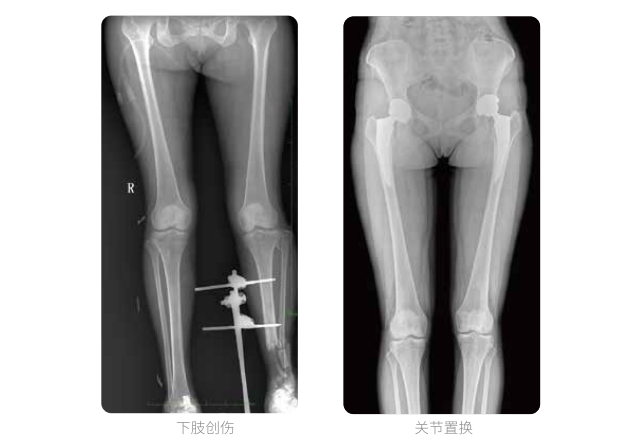

髓内钉手术是骨科、手足外科中常见的微创型手术方式,患者随访时需拍摄置入在股骨、肱骨处的较长髓内钉。PLX8600视野拍摄,能够出色解决医生需多次摄影再拼接的痛点。一次成像双下肢,即拍即得,高效率,无需拼接。工作站软件自带的测量功能方便医生读取双下肢长度数据,助力准确诊断。

动态DR所具备的全脊柱、全下肢全景成像技术检查,能够更加清晰的显示患者病情变化情况,对骨科疾病患者的全脊柱、全下肢病变情况图像展示更加具有完整性,对患者在自然状态下的应力情况展示较为全面,有助于骨科疾病患者临床诊断效果的提升,对患者临床治疗方案的科学制定有着积极的作用。